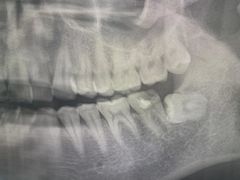

• 牙博士口腔品牌连锁(杨浦店)

艾力克斯_234 | 22-03-19

报错